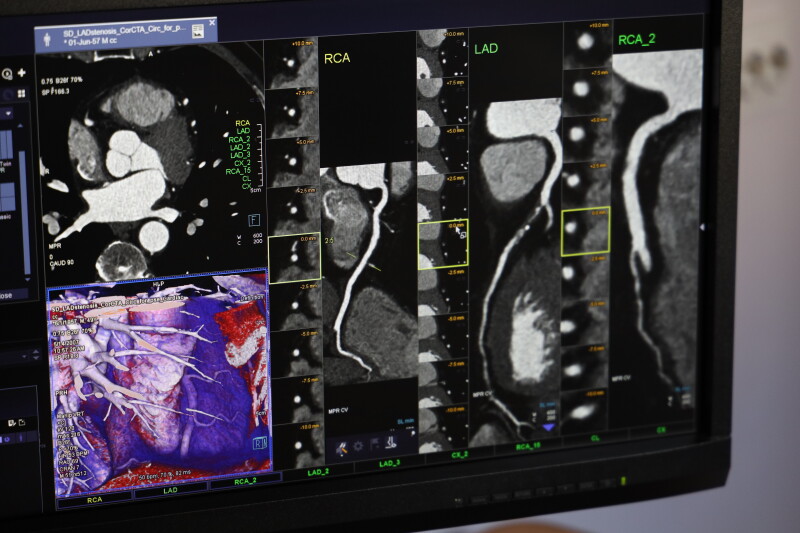

Шестидесятичотирьохсканний комп’ютерний томограф — одне із найкращих досягнень у медтехніці станом на сьогодні. Таких апаратів лише три в Україні. Один з них – у міській лікарні Луцька. Також в приймальному відділенні є ендоскопічний кабінет та кабінет ультразвукової діагностики.